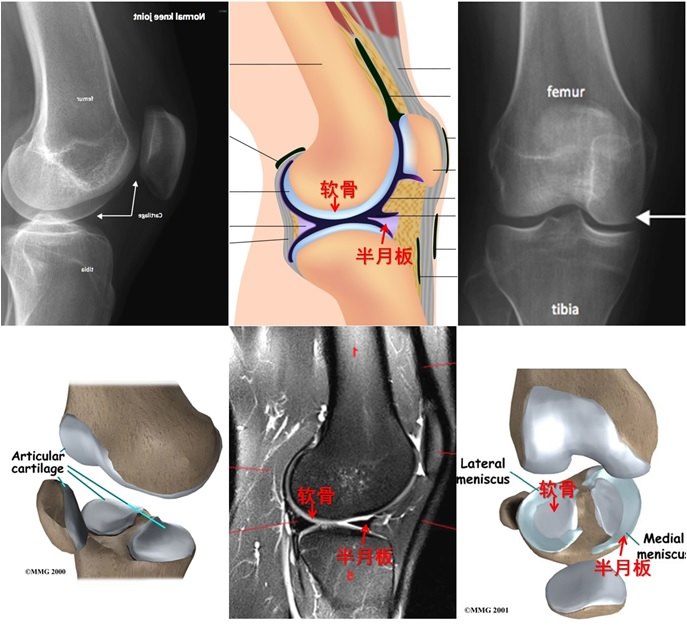

经常会遇到有人发现自己“关节疼、肿”,到医院拍片,诊断为“滑膜炎”(图1a,1b)、“骨质增生”(图1c,1d,1e),还有诊断为“关节炎”的(图1d,1e)。那到底是那种病?我们对这几种病名分别了解一下。

图1.膝关节的各种X线拍片表现

图2A.正常的关节:可见关节面软骨(“轮胎表面”)和半月板(“垫片”)。

图2B.关节软骨损伤继发滑膜炎。过度活动、退变导致关节面软骨损伤,产生碎屑;碎屑刺激关节腔滑膜,滑膜增生变厚,分泌滑液,关节积液,导致“滑膜炎”。